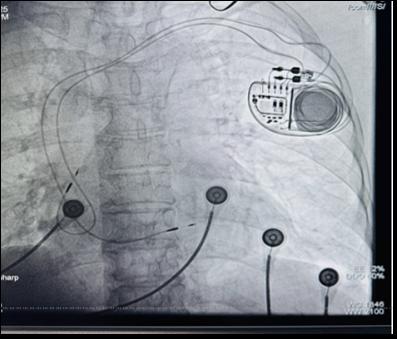

近日,我院心血管内科胥勇斌主任团队在高金全院长的指导下成功完成崇州市首例全生理性起搏手术(详见图1),这一突破性进展不仅填补了区域心脏起搏领域的技术空白,更以 Bachmann 束起搏、左束支区域起搏为核心,为心律失常患者带来了 “最接近心脏自然节律” 的治疗新选择,标志着崇州市心脏起搏治疗正式迈入 “精准生理性” 新阶段。

77 岁的周大妈长期受心动过缓困扰,最慢心率仅 43 次 / 分,日常活动后常出现气短、精神萎靡等症状,经详细检查确诊为 “房室传导阻滞”。 我院心血管内科团队综合评估患者后分析若采用传统部位起搏,可能因心房间、心室间电信号传导不同步,影响心脏整体协调性,甚至增加远期房颤、心衰风险。团队最终决定采用 Bachmann束起搏加左束支区域起搏的创新方案,通过双部位精准起搏,重建心脏自然电传导路径。

图1:胥勇斌主任团队为患者实施全生理性起搏治疗

手术团队分两步精准构建了生理性起搏体系。首先成功行右心室左束支区域起搏(详见图2),使 QRS 波宽度缩至 93ms(达到健康人群正常范围),确保左右心室同步收缩,避免传统右室心尖起搏导致的心室不同步问题;随后团队将心房电极精准植入Bachmann束区域成功行Bachmann 束起搏,起搏时见P 波时限更高更窄(P波由 119ms直接缩短至 100ms,P波高度增加(详见图3、图4)。